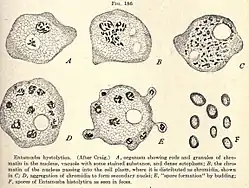

Illustration (1910): E. histolytica Lebensstadien

Illustration (1910): E. histolytica Lebensstadien -